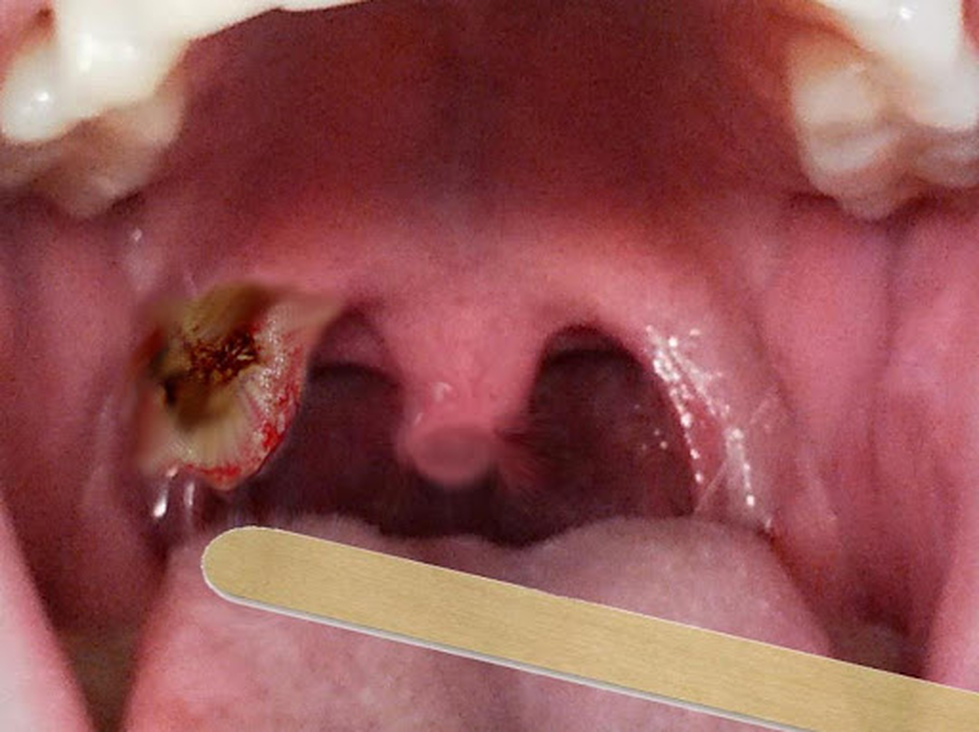

- Cụt lưỡi gà: Một số trường hợp, tế bào ung thư sẽ ăn đứt lưỡi gà và tạo thành lỗ hổng trong miệng làm thức ăn không thể xuống dạ dày để tiêu hoá mà trào ngược lên vùng mũi, khiến bệnh nhân gặp nhiều khó trong việc ăn uống.

- Ho ra máu: Tế bào ung thư gây ra viêm nhiễm, lở loét nặng khiến bệnh nhân thường xuyên ho và khạc đờm ra máu. Vùng tai, mũi, họng cũng có thể chảy máu kèm theo choáng váng, suy giảm chức năng.